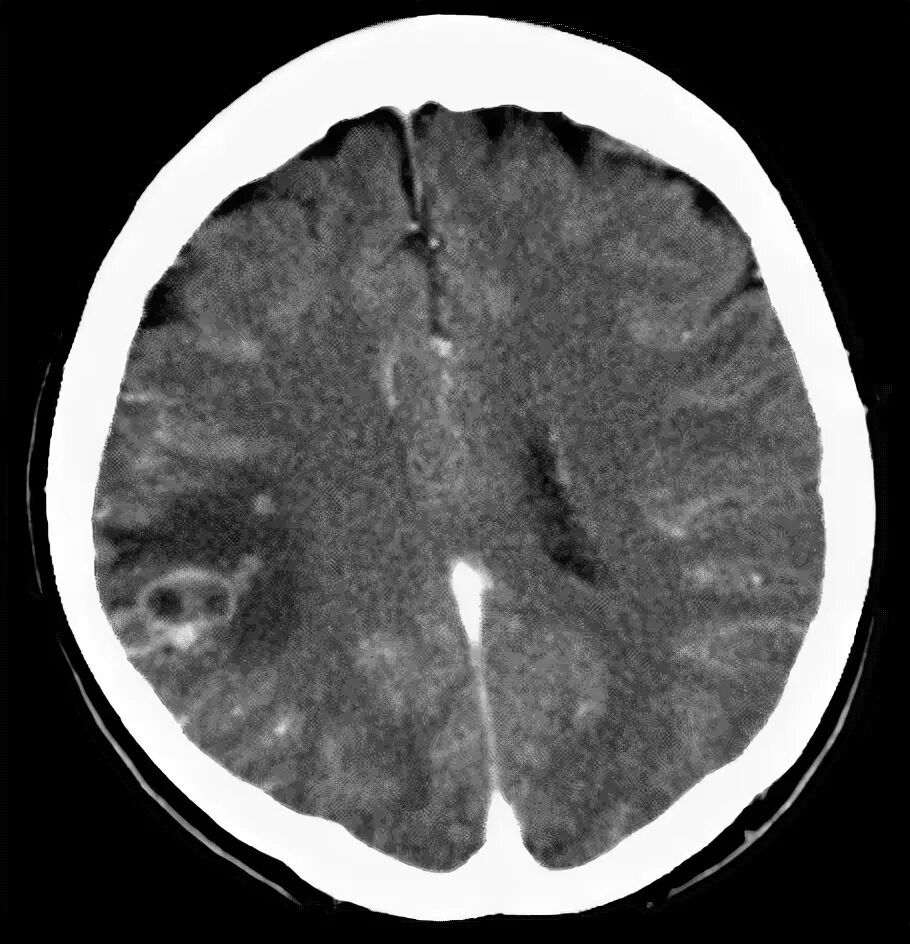

Ошибки кт